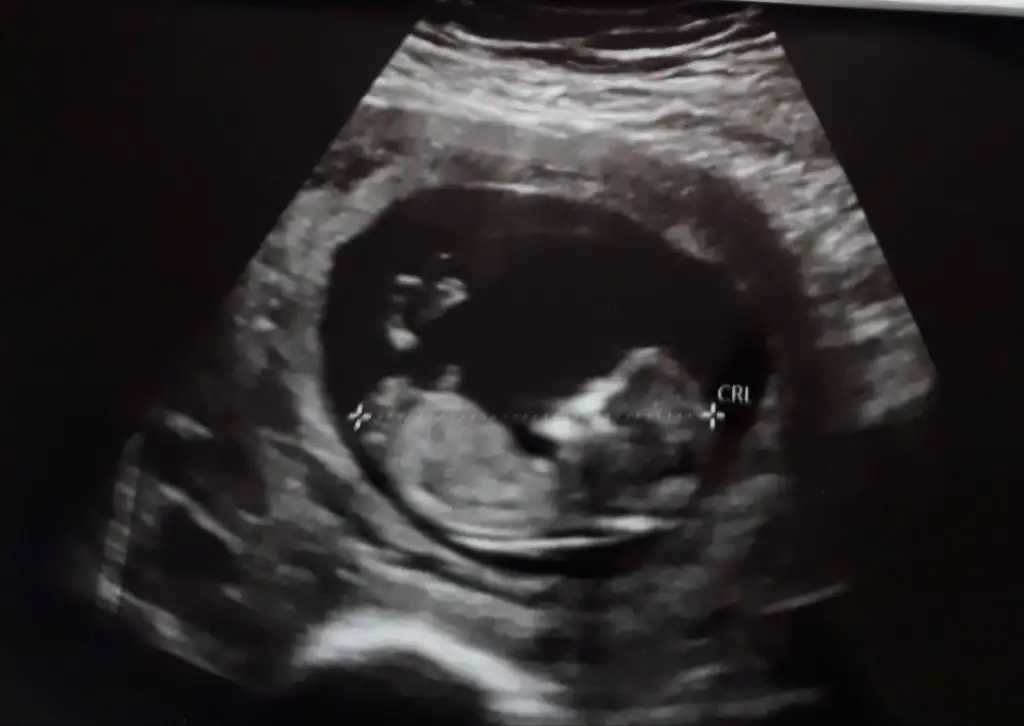

4 yil oncesinden kendimi buldum. Oglumda tutturamadik ama azimliyim 12. Hafta ultrasonuyla bu sefer yeniden dener miyizEki Görüntüle 2012571 kizlar var mi bi fikriniz

Nubu gözüküyor mu acaba ben anlayamıyorum yoksa başka bir yerden mi anladınız kız oldugunuKız görünüyor

Erkek gibi nubu dik görünüyor12 haftalik usg yorum yaparmisiniz rica etsem